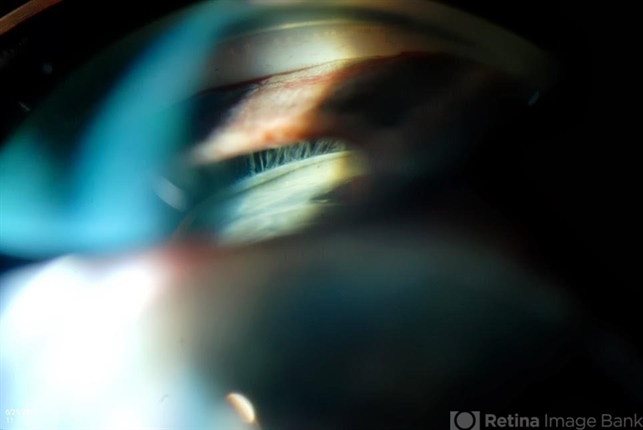

- Zonules

- Jason S. Calhoun, Department of Ophthalmology, Mayo Clinic Jacksonville, Florida

Photo slit lamp biomicroscope

TOPCON D-90 SL NIKON CAMERA - Description

- Visible zonules that are shown through goinoscopy after surgery. Blood also in the trabecular meshwork.